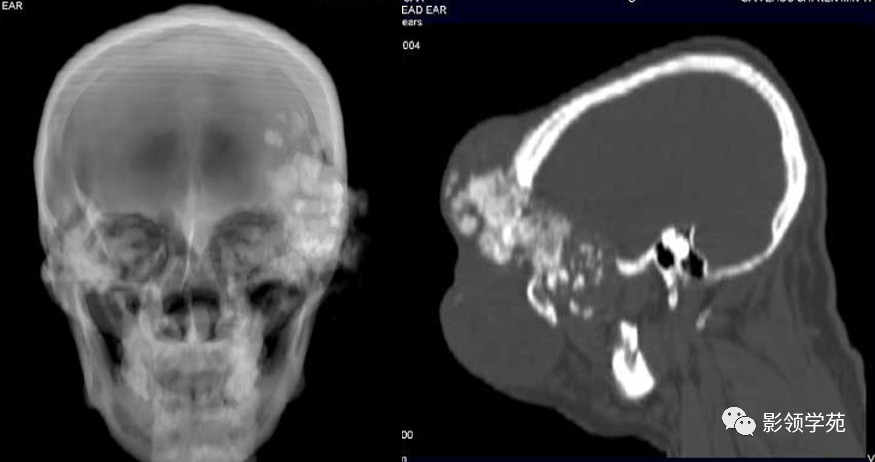

额骨骨纤维肉瘤并肺部转移